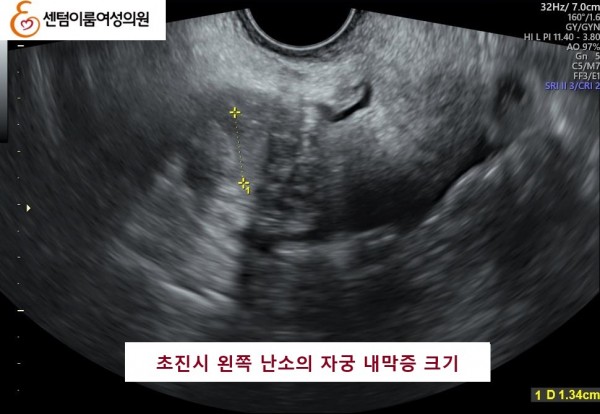

2025.6.28 본원에 내원시 양측 자궁 내막종이오른쪽 4.5cm , 왼쪽 1.3cm 정도 였습니다.

본 원에서 수술없이 알콜경화술 3개월 후 양측 다 사라진 사례입니다.